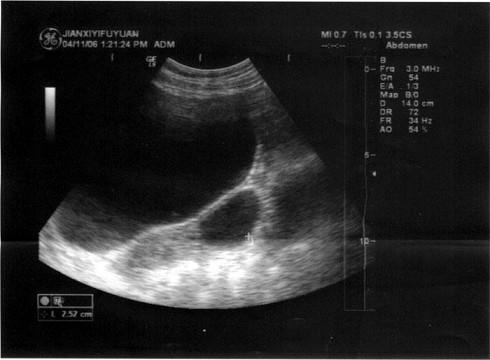

问题 女,25岁,B超检查如图所示,最可能的诊断为?(?)

选项 A.左卵巢癌 B.左侧输卵管积液 C.左卵巢卵泡 D.左卵巢囊肿 E.扩张的左侧输尿管

答案 D